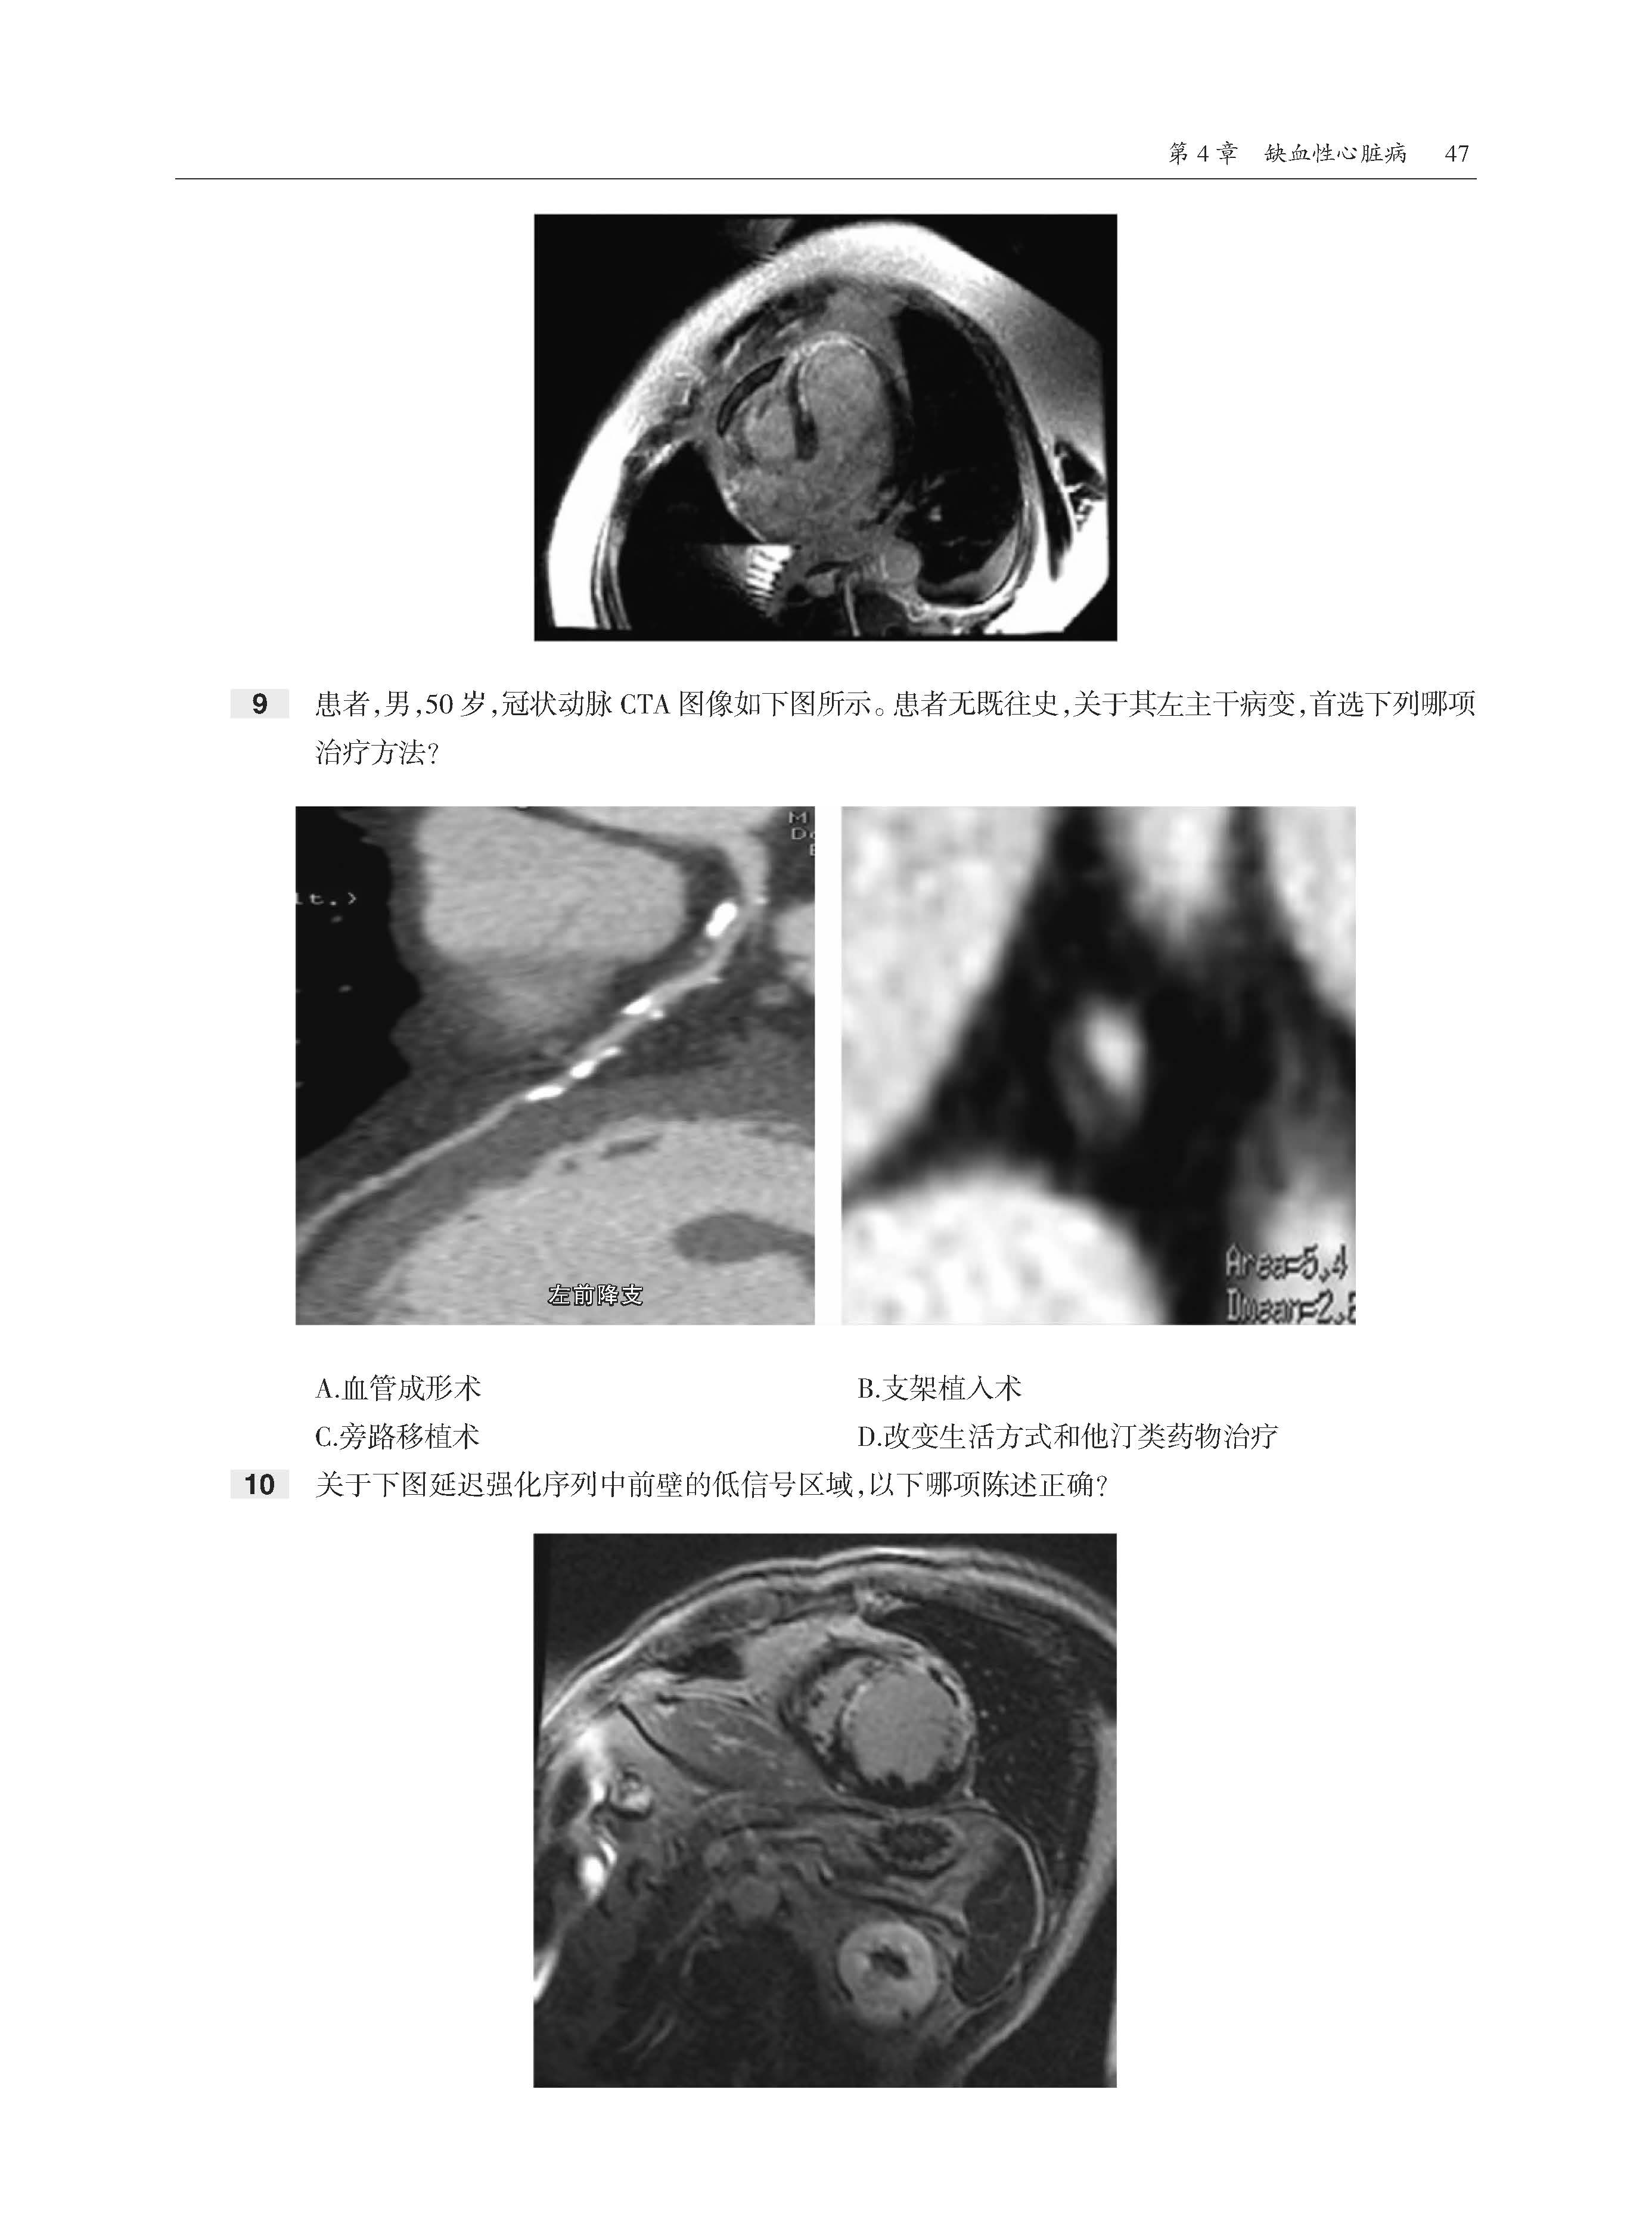

全书共11章内容,首先介绍了心脏放射成像基础和生理学基础,然后分别论述了缺血性心脏病、心肌病、心脏肿瘤、瓣膜病变、心脏周围病变、先天性心脏病、胸主动脉和大血管获得性病变,以及设备和术后表现。书中内容采用问答体例,各章开始均先给出患者影像图片和问题,供读者分析解答。在每章末尾给出问题答案,供读者参考。此书最大的特点是基于临床问题的多项选择题形式,每个选择题附有详细的解答,正确选项和错误选项均有详细的注释。该书全面回顾了心脏影像学的诊断要点,有助于读者理解和系统掌握心脏病变影像特点和诊断思路。

·300多道选择题,每道题都给出了答案、解析和相关参考文献。

·大量高清图像,直观展示病变。